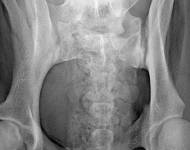

(3) 7 měsíců VD 1

(3) typ 3 po korekci polohy pánve